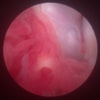

関節鏡検査を実施いたしました。関節鏡検査では、重度の滑膜炎および前十字靭帯の完全断裂が認められました。半月板に損傷は認められませんでした。

関節穿刺を行い、好中球はなく、少数のマクロファージや滑膜細胞が認められるました。膝蓋骨脱臼および前十字靭帯断裂による退行性の関節炎を疑い、関節鏡検査を実施いたしました。関節鏡検査では、重度の滑膜炎および前十字靭帯の完全断裂が認められました。内外側とも半月板に損傷は認められませんでした。